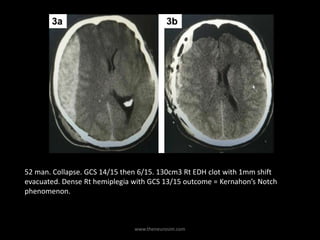

52 man. Collapse. GCS 14/15 then 6/15. 130cm3 Rt EDH clot with 1mm shift

evacuated. Dense Rt hemiplegia with GCS 13/15 outcome = Kernahon’s Notch

phenomenon.